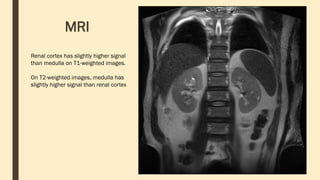

MRI

Renal cortex has slightly higher signal

than medulla on T1-weighted images.

On T2-weighted images, medulla has

slightly higher signal than renal cortex